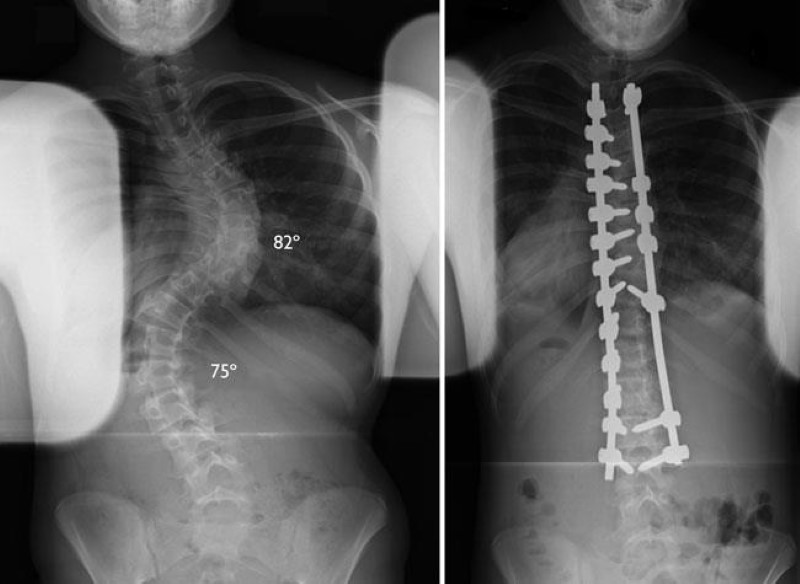

Back braces are not often used in adults with scoliosis but they can provide pain relief by supporting your spine. When a person is diagnosed with severe scoliosis meaning their Cobb angle is over 45 degrees spinal-fusion surgery is often recommended. Starting in the late 1990s surgeons started using newer techniques to fuse the spinal column.

Full recovery takes 6 to 12 months so it is not a process that should be taken lightly. With the tools and technology available today scoliosis surgeons are able to improve curves significantly. The Providence brace a brace worn only at night is.